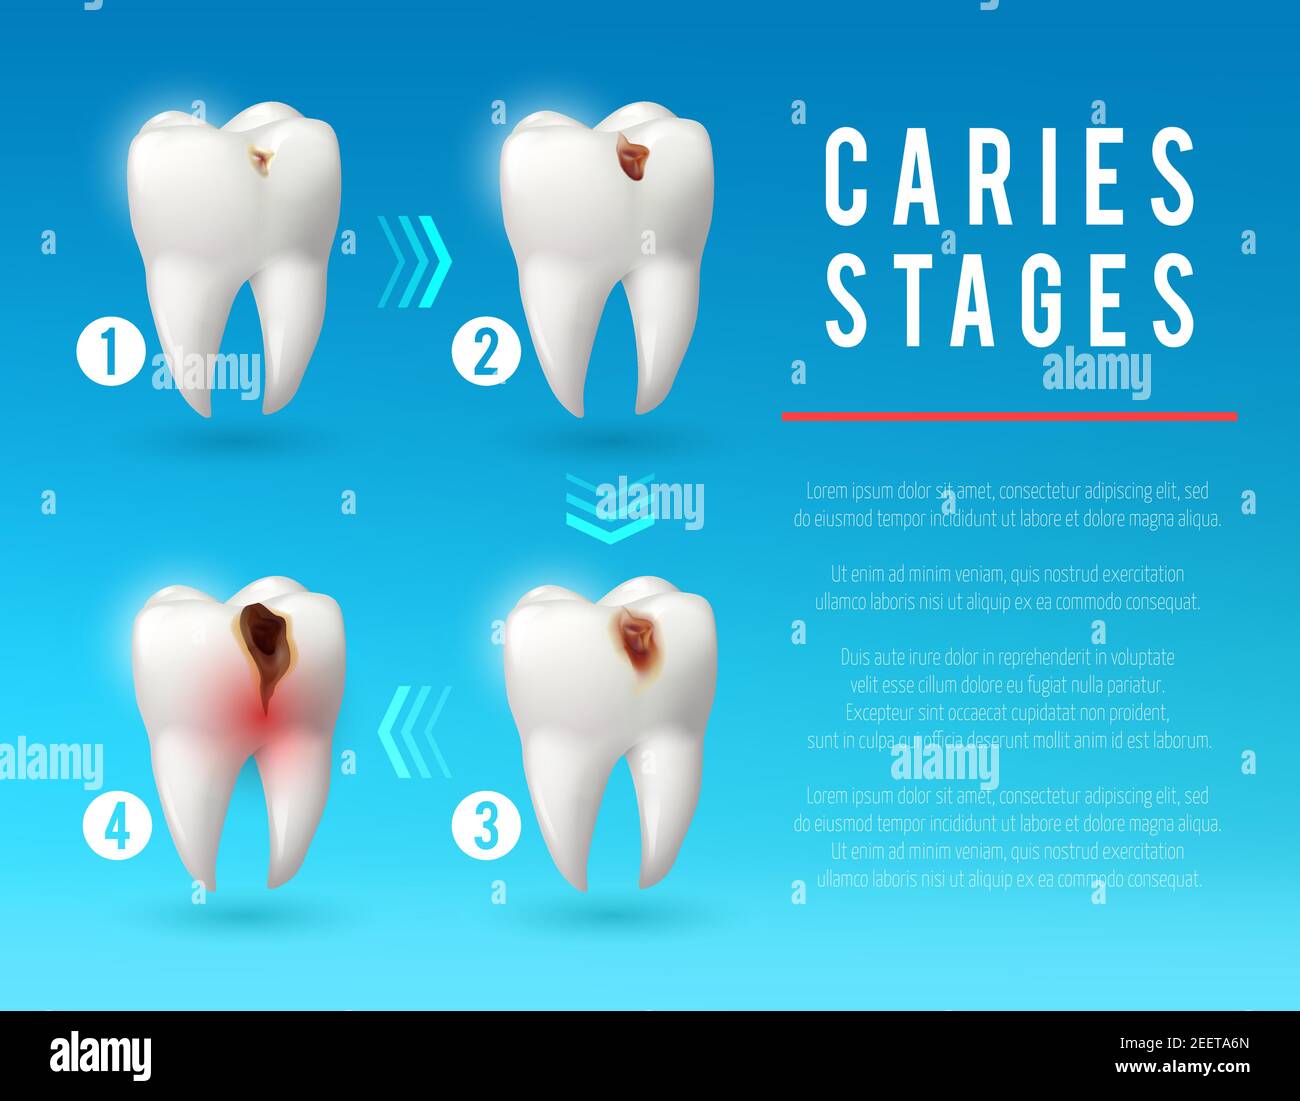

Cute Cartoon Tooth Character Show Stages Of Caries Development. Stock

www.dreamstime.com

www.dreamstime.com

caries tooth stages development character cartoon cute show dental illustration background blue preview

Tooth Decay 3d Vector Poster. Teeth On Different Stages Of Dental

www.alamy.com

www.alamy.com

caries decay tooth teeth stages infection enamel dentin pulp